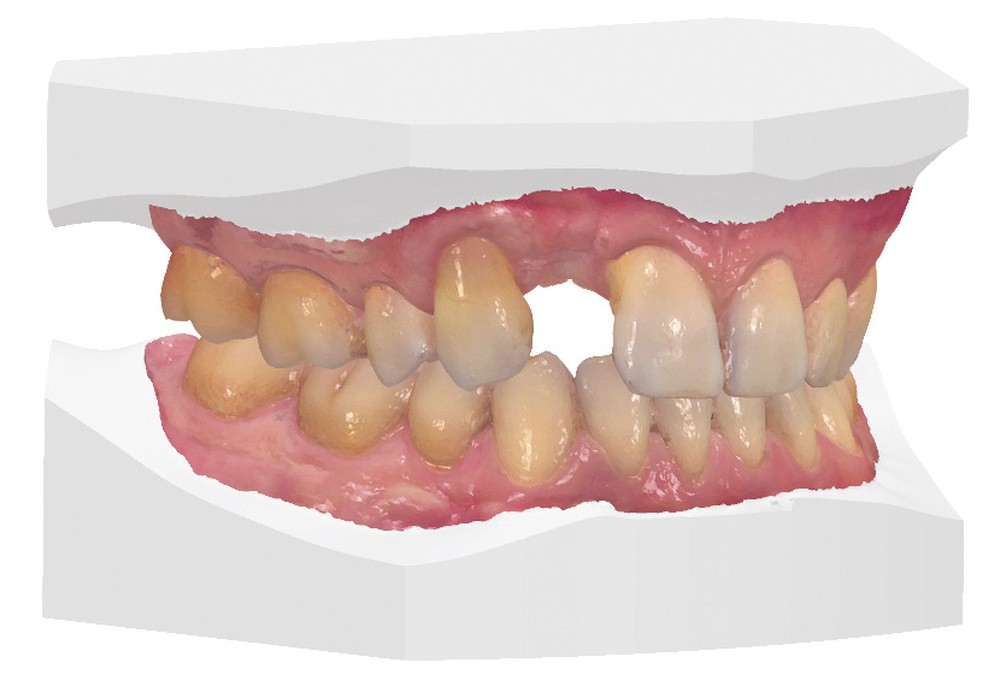

Un patient de 44 ans, n’ayant comme antécédents médicaux qu’une addiction au tabac, présente une agénésie des incisives latérales supérieures. L’incisive latérale gauche lactéale (62) a été traitée de longue date par une facette céramique satisfaisante sur le plan clinique et esthétique (fig. 1a). L’incisive latérale droite lactéale (52) a été extraite à la fin de son adolescence et remplacée par une prothèse fixe implanto-portée pendant plus de quinze ans.

Une péri-implantite sévère a nécessité la dépose de ce premier implant. Le nouvel implant mis en place à la suite de ce premier échec a dû être également retiré après une perte d’ostéointégration secondaire. Une prothèse amovible partielle a alors été retenue comme solution de temporisation (fig. 1a-b).

L’analyse de la situation clinique montre une ligne du sourire basse (classe 4 selon Liébart et coll. [22]) (fig. 1c). La perte tissulaire parodontale de classe III (selon Seibert et coll.) située au niveau de l’incisive latérale droite (12) est la conséquence des différents échecs rencontrés. Ce défaut tissulaire est associé à une perte d’attache parodontale (fig. 1d) sur les deux dents adjacentes (11 et 13), entraînant une forte asymétrie de l’alignement des collets (fig. 2). Le patient est en occlusion de classe I d’Angle bilatérale et présente un guidage canin fonctionnel.

La situation clinique est transférée au prothésiste au moyen d’empreintes optiques (Trios 2, 3Shape) pour une conception numérique de la prothèse (fig. 8 et 9).